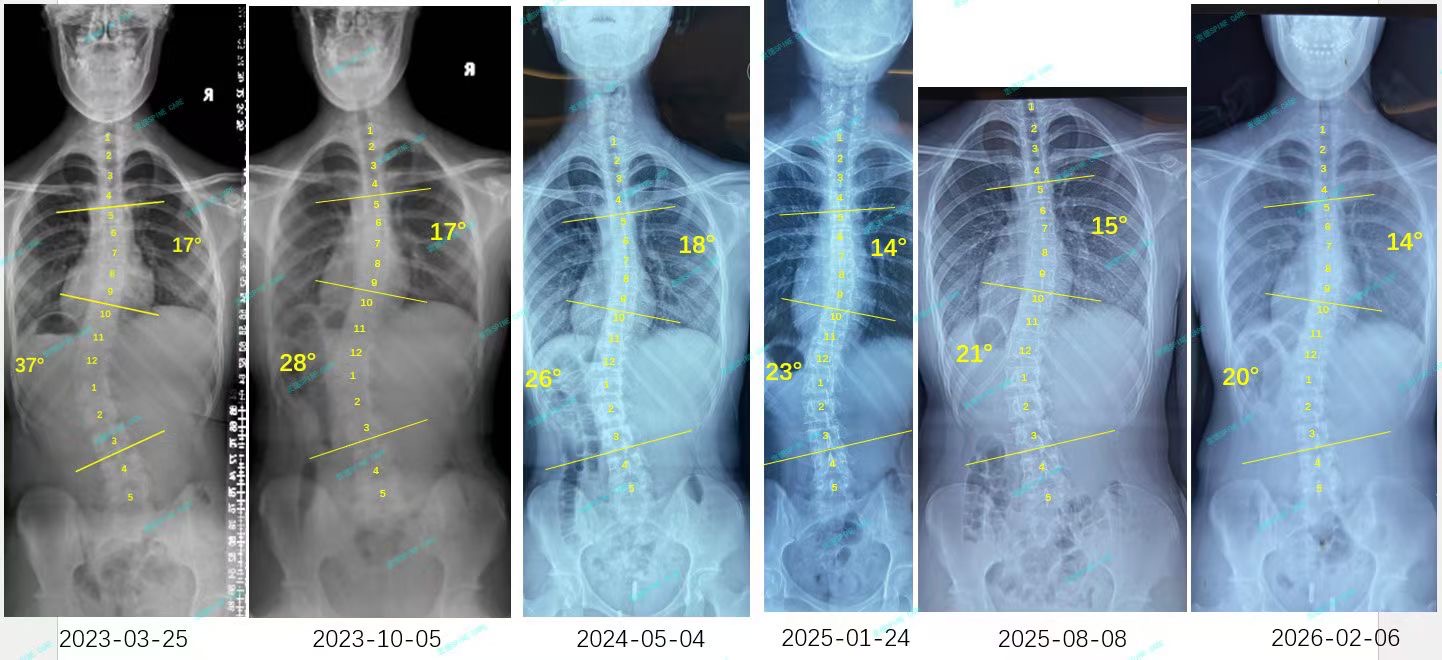

来自家长对衷德的评价(小欣妈妈)